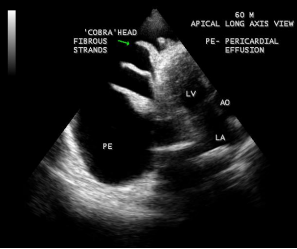

The other echocardiographic manifestations of burnt-out endomyocardial fibrosis are shown in Figures 29 to 44 as given below

Figure 29: 2D Echocardiographic imaging showing massive pericardial effusion with ‘cobra-head’

fibrous strands in the pericardial sac suggesting the burnt- out stage of endomyocardial fibrosis in a 60-year old male.

A large pericardial effusion is often present and noted as another peculiar feature of this disease [27]. Pericardial effusion and ascites dominate the clinical picture of right ventricular EMF [28], [29], [30]. Etiology of pericardial effusion is possibly inflammatory and EMF is to be considered as ‘pancarditis’ since all the layers are involved. Adhesions between the parietal and visceral layers of the pericardial sac may develop and visible as strong fibrotic strands as shown in Figures 29. A right ventricular EMF presented with massive pericardial effusion was detected in a 85 –year old female as shown in Figure 16, 17 and 29[31]. Cardiomegaly can be exaggerated by pericardial effusion, and pleural effusion is also a common finding as shown in Figure 9 [16-Figure 2]. Giant ascites in EMF is not fully explained by congestion alone and it is due to peritoneal inflammation and reduced reabsorption of peritoneal fluid, caused by fibrosis since the fluid is an exudate with predominant lymphocytes. The triad of elevated JVP (Jugular venous pressure), ascites and hepatomegaly formed the hallmark of right ventricular EMF.

Today echocardiography is used as the screening tool at the community level as the diagnosis of EMF could be confirmed at the bedside. Echocardiography accurately assesses the pathological abnormalities of chronic disease and it is the gold standard technique for the diagnosis of EMF [36]. It reveals dense endomyocardial echocardiograms along different parts of the mural and valvular endocardium and AV valve dysfunction [37] as shown in Figures 3 to 44. The typical feature of EMF is the obliteration of trabecular portion of the ventricle and in advanced cases, there is shrinkage of the cavities creating an apical notch, regurgitation, slow flow with spontaneous echo contrast as in Figure 36 and considerable pericardial effusion. Similar to apical notch of right ventricle, a right atrial notch is well seen as contraction (or retraction) of tricuspid annulus as in Figure 40 and right atrial notch as in Figure 41 and 42, indicating the retraction of rightatrial cavity as a peculiar feature of right ventricular EMF. Biventricular enlargement as shown in Figure 40 and biatrial enlargement as in Figure 32 are the characteristic features of advanced stage of EMF. The fibrosed muscular trabeculae extending into the cavities from the walls of the chambers in the right ventricle visible as ‘cobra heads’ as in Figure 4 and in pericardial sac as in Figure 29, in the left ventricle. Aneurysmal right ventricle with scattered areas of fibrosis in the sub tricuspid region and a notch in the right atrium is well seen in a 14 –year old boy as in Figure 42 . Right atrial notch is frequently noticed in EMF patients as shown in Figure 41 in a 47- year old male with left ventricular EMF and moderate pericardial effusion.